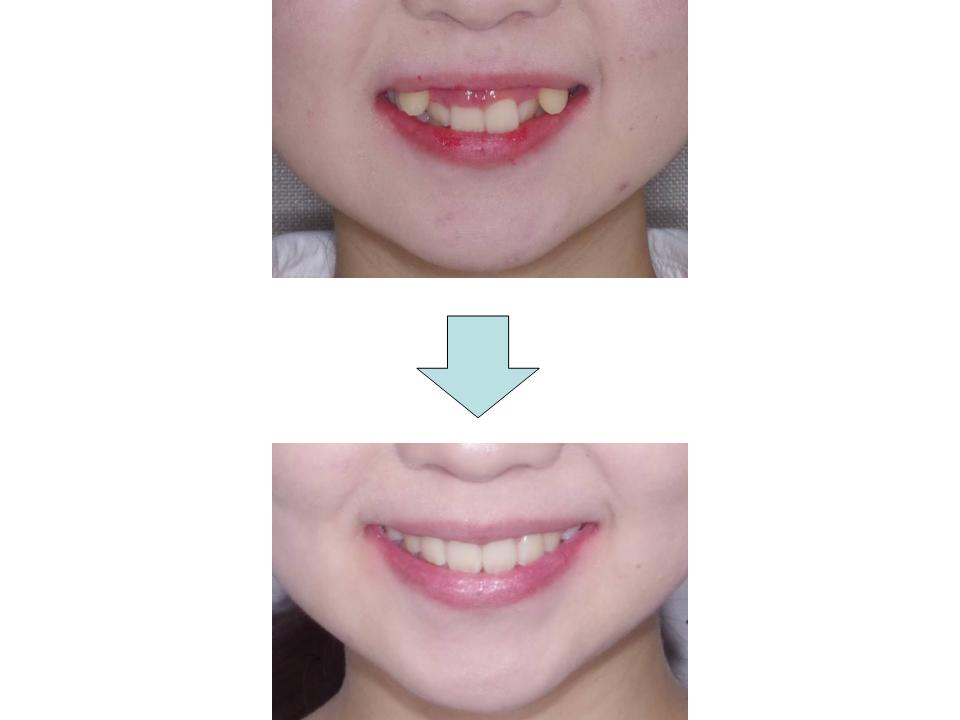

八重歯、上の前歯が出ている

上下前歯の凸凹が大きく、歯とあごの大きさのバランスの乱れを認めたため、上下の歯の抜歯を行って前歯の凸凹を改善しました。患者さんの装置装着状況も良好で上下の歯をきちんとかみ合わせることができました。

| 主訴 | 八重歯、上の前歯が出ている |

| 年齢・性別 | 30歳 / 女性 |

| 抜歯部位 | 上下顎両側第一小臼歯 |

| 装置 | マウスピース型矯正装置(インビザライン) |

| 期間 | 2年10か月 |